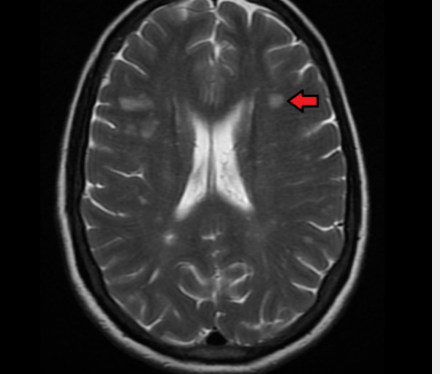

多发性硬化症是一种脱髓鞘疾病,其特征是大脑神经细胞绝缘层受损。多发性硬化症没有已知的治愈方法,长期结果也难以预测。MS是影响中枢神经系统的最常见的免疫介导疾病,全世界有2-250万人患有这种疾病。现在,UCL领导的一项新研究发现,早期MRI扫描可用于预测疾病的进展。

预测多发性硬化症的结果非常困难。女性,尤其是那些早期患MS的女性,通常比男性面临更少的不良后果。据估计,MS患者的预期寿命比健康人短5-10年,但其中40%的人能活到70岁。MRI通常用于诊断疾病,但现在科学家认为它也可用于预测其进展。这可以帮助为每个人创建量身定制的治疗方案。

科学家们发现了164名患有临床孤立综合征(CIS)的人,并对他们进行了15年的跟踪调查。CIS患者通常也会继续患有MS。经过15年的研究,科学家们找到了参与者并评估了他们的残疾程度。57%患有复发型多发性硬化症,15%患有继发性进展型,27%仍患有CIS,1%患有其他疾病。研究人员查看了这些人在长期研究期间收集的MRI,发现早期脊髓损伤表明患者更有可能继续发展为继发性进行性多发性硬化症。换句话说,MRI分析允许预测每个参与者未来的残疾水平。

能够准确预测MS的进展极为重要。这有助于制定更有效的治疗计划,而且患者自己也知道他们在不久的将来可以期待什么。大量研究表明,早期强化治疗可带来更好的MS预后。然而,当你不知道会发生什么时,做出这样的决定是很困难的。MRI测试可以帮助使这些预测准确。

MS患者已经在使用MRI进行测试。现在科学家们必须制定指导方针,让医生知道该看什么以及会导致什么特定症状。希望这将帮助全球数百万MS患者。